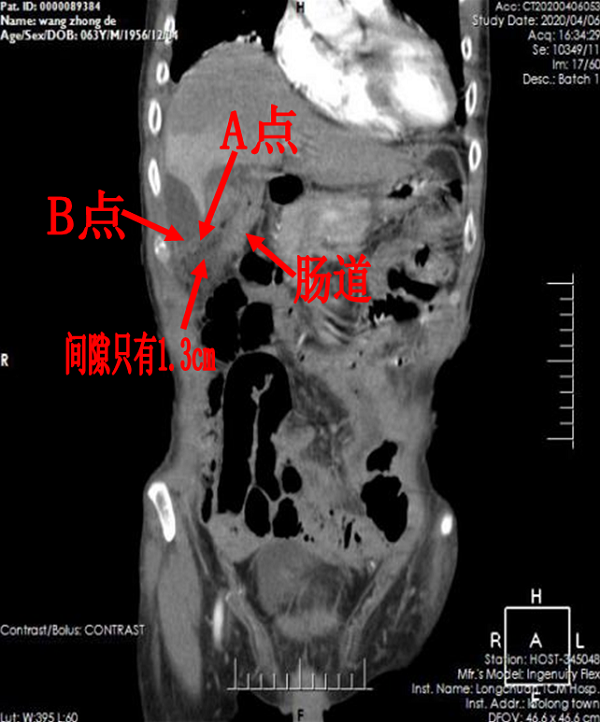

与此同时,腹部增强CT提示患者胆囊穿孔,游离气体溢出腹腔,并腹腔多处脓肿形成,感染较重导致炎症指标明显升高,不排除逐渐发展至感染性休克的风险,病情危急。

患者高龄且存在较为严重糖尿病,这些均为治疗胆囊穿孔并脓肿的严重不利因素。有鉴于此,李嘉医生与科室主任谢闻文向医务科汇报,在受援医院领导的协调下组织了全院MDT讨论。MDT讨论最终确定出先行B超引导下精准穿刺,如穿刺效果不理想,随时准备腹腔镜探查的治疗方案。

4月9号下午四点,在完善各种医疗文书工作以及各项术前准备后,李嘉医生在B超引导下对患者行腹腔多发脓肿精准穿刺引流。该院B超室团队细致、耐心地引导穿刺导丝以及穿刺针成功地在不到1.3cm的间隙中,避开了肠道以及右肝外叶,将5mm的引流导管头部精准引导入肝下脓肿处。同时引流导管侧孔无偏差地对准于肝肾隐窝脓肿处,精确地引流出两处脓肿,完美地达到术前既定方针。

引流管走向示意图,避开右肝下缘、肠道